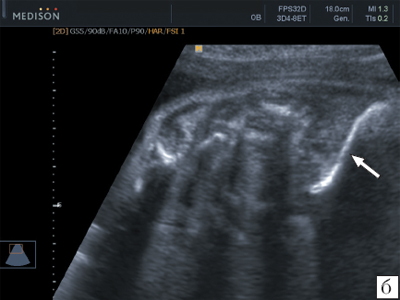

- Ультразвуковое исследование доброкачественного образования.

- ультразвуковой анализ;

- Ультразвуковое обследование образования.